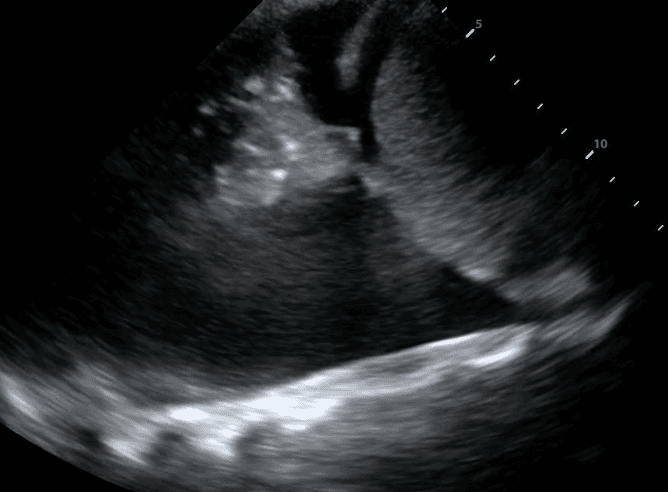

If a pleural effusion is present, there will be an anechoic (ie. black) space above the diaphragm. Please note that an anechoic space below the diaphragm represents ascites; not a pleural effusion. Two other other features will stand out to you. Firstly, you will see a “spine sign.” Normally, the spine cannot be visualized above the diaphragm since aerated lung scatters ultrasound beams before it can reach the spine. However, a pleural effusion will allow sound waves to be transmitted to the spine and you will see the spine clearly visible above the diaphragm.

Secondly, you will see a consolidated lung sitting in the effusion. Please refer to our post on consolidations to learn what consolidated lung looks like. If the effusion is large, the consolidated lung will appear to float in the effusion - resembling a jellyfish swimming in the ocean. This is referred to as the “jellyfish sign.”

Estimating the size of a pleural effusion can help determine if, when and where the effusion can be drained. Effusion size may be qualitatively classified as small, medium or large. If there is a “jellyfish sign,” the effusion is at least moderate to large in size.